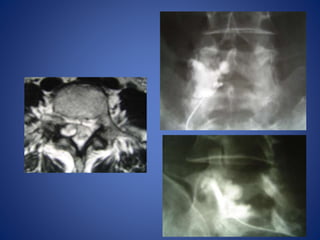

CT scan of a patient with spinal canal stenosis

at the level of L5 due to facet joint arthrosis

Clinical signs and radiologic appearance

in accordance

CT scan ofa patient with spinal canal stenosis at the level of L5 due to facet joint arthrosis

Clinical signs andradiologic appearance in accordance